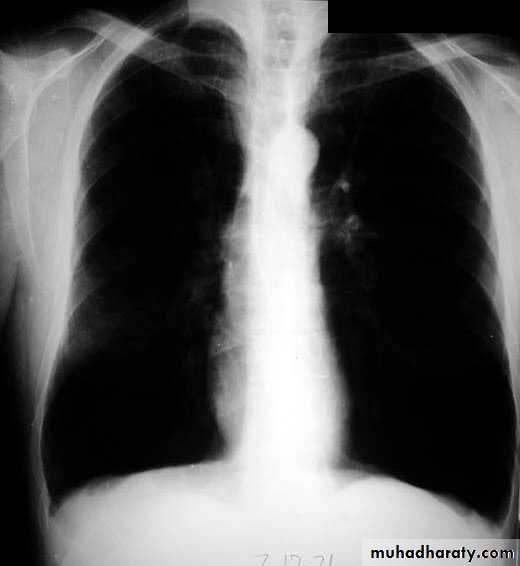

X-ray views1- PA view.

NORMAL PA view